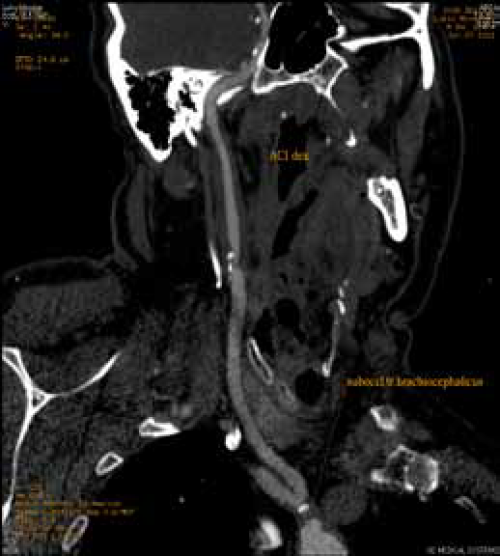

Visokostepena stenoza karotidne bifurkacije (80%) heterogenim plakom sa ulceracijom prema unutrašnjoj karotidnoj arteriji. MSCT potvrdjuje subokluziju karotidne bifurkacije i isključuje proksimalne i distalne lezije.

Krataka segmentna aterosklerotična okluzija unutrašnje karotidne arterije. Prikazuje se spoljašnja karotidna arterija sa svojim granama i plakom na orificijumu

MSCT – precizna analizua morfologije lezija supraaortalnih arterija

Skoro potpuna okluzija brahiocefaličkog trunkusa sa dugačkom totalnom trombozom zajedničke karotidne arterije levo